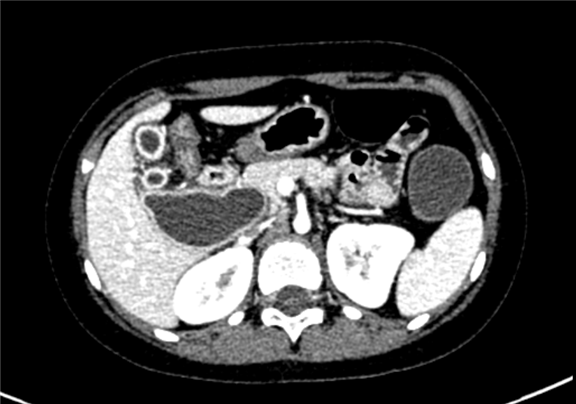

上腹部增强CT:先天性胆管囊状扩张(IV型)可能性大,胆总管十二指肠胰腺段及十二指肠壁内段显示不清, 胆囊壁增厚,肠系膜根部散在散在略大淋巴结

术前CT检查:

动脉期

静脉期